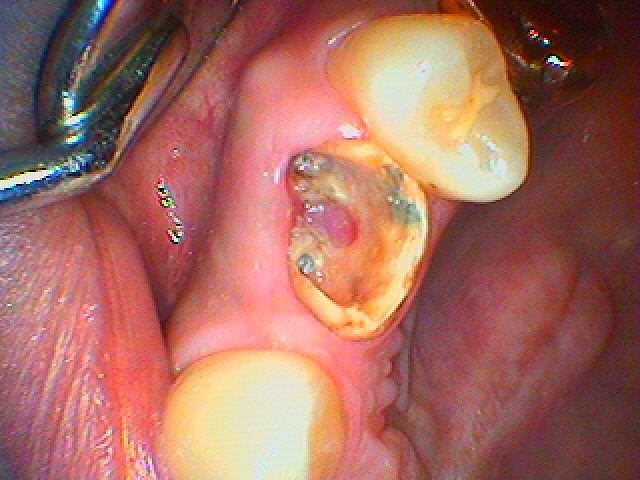

ブログ一覧|広島市安佐南区の歯科医院 ブログ一覧 トップ ブログ一覧 お知らせ スタッフブログ ブログ一覧 お知らせ 2020/04/18 自分が使っているインプラントはほぼ補填材にてインプラントを固定しているにも関わらず3ケ月にはこのようにしっつかりとつき驚かされます お知らせ 2020/04/18 左上5番 土台ごと被せが脱離、診てほしい ブリッジか、インプラントか? お知らせ 2020/04/17 最終上部構造の作成になります アバットメントからのセラミックにて綺麗に作成しています お知らせ 2020/04/17 左下6番の ヘミセクションしてある歯のインプラント埋入 硬いものを噛むと痛むとのこと お知らせ 2020/04/16 左上4番の歯肉形態の付与からの最終補綴形態へ 審美領域のインプラントは一工夫が必要となります お知らせ 2020/04/16 左上4番の歯が先天性欠如 乳歯を40歳になるまで使用してきたが、いよいよだめになった 診てほしい インプラントか? 隣在歯を削合してブリッジか? お知らせ 2020/04/16 前歯部の骨造成インプラントケース 最終補綴の完成 お知らせ 2020/04/15 2本のインプラントを骨幅が狭いところはリッジエキスパンジョンを行い何とか埋入し増骨処置GBRを行って骨幅を大きくさせています << 1 2 3 4 5 … 339 340 341 342 343 … 870 871 872 873 874 >> Web診療予約 初めての方へ 選ばれ続ける理由 院内設備について 歯が痛いしみる一般歯科 歯がぐらぐらする歯周病 健康な歯を保ちたい予防歯科 子供の虫歯予防をしたい小児歯科 銀歯をセラミックに審美歯科 白い歯を目指しませんか?ホワイトニング 矯正専門医がいるので安心矯正歯科 抜けた歯を補いたいインプラント・入れ歯 医院案内 スタッフ紹介 メリィハウス歯科クリニックオフィシャルホームページ ラベンダー歯科クリニックオフィシャルホームページ お知らせ・ブログ ホーム 診療科目 一般歯科 歯周病治療 予防治療 小児歯科 審美治療 ホワイトニング 矯正歯科 入れ歯・インプラント マウスピース矯正 初めての方へ 院長・スタッフ 設備紹介 医院案内・アクセス メニューを閉じる